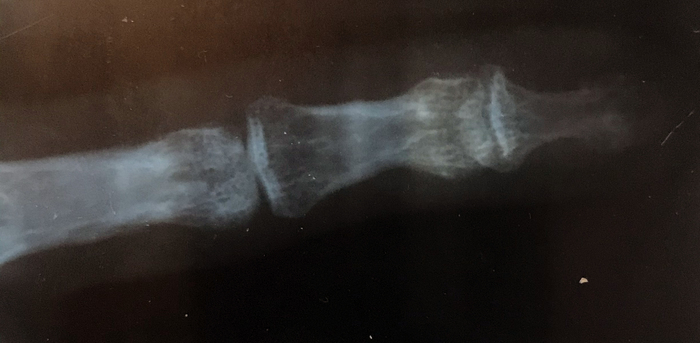

В 2019 году получил травму мизинца на левой руке в ходе выяснения отношений с одной пьяной тушей. Какая-то там травма пальца была не то, что на втором или третьем месте - я вообще это всерьёз не воспринимал. Быстро сходил в травматологию, сделали снимки, наложили повязку, что-то сказали и отпустили. Как только я переступил порог медицинского заведения, все мысли об этом меня покинули, и я опять погрузился в бытовуху. Да, это жёстко, когда человек забивает на себя и своё здоровье, жёстко, когда отношения летят в тартарары и ты вместе с ними, падая, периодически во что-то впечатываешься: "Опа, дно!". А потом "ой, нет, ещё не дно" - и так далее. И вот, я, Граф, мать его, Монте Кристо, вырываюсь из однокомнатного замка порочного круга, который я сам же себе когда-то создал, и мало-помалу начинаю приходить в себя, больше включаться в работу, налаживать отношения с внешним миром. Стал обращать внимание на своё здоровье: посещал стоматолога, гастроэнтеролога, лора, терапевта, ходил на лечебный массаж. Не обошёл стороной и травматолога, поскольку палец периодически не давал покоя - десятипальцевый набор текста, игра на гитаре, клавишах - всё это даёт нагрузку на связки, из-за чего под вечер палец начинает ныть и я закидываюсь обезболивающим.

Вердикт травматолога был такой: признаки неправильно сросшегося перелома основания дистальной фаланги со смещением. К дистальной фаланге подходят две связки - сгибатель и разгибатель. При травме откололся кусок кости, куда прикреплялся разгибатель, а потом это как-то неправильно срослось, палец внешне слегка выглядит деформированным. До конца не разгибается, при движении периодически пощёлкивает сустав. В 2020 году я получил квоту на операцию (только теперь сам не знаю, что за операцию и как они там собирались делать, я был уверен, что починят норм), сдал анализы и 2 апреля должен был явиться к ним. Ну а накануне, 1 апреля мне сообщили, что из-за ковида остановлены все плановые операции и шёл бы ты нахер, ну да, ну да. В общем, никто ничего толком не знал, я обзвонил всё, что только можно было обзвонить касательно моего вопроса и понял, что остался ни с чем. Спустя некоторое время я перебрался из своего Шира в славный город-на-Неве, Санкт-Петербург (вернее, в Ленобласть, и поначалу мне казалось, что я в Ашхабаде или Биробиджане, но сейчас привык). В Санкт-Петербурге есть отличный центр ортопедии и травмотологии ФГБУ "НМИЦ ТО им. Р.Р. Вредена". Ходят слухи, что там работают вредины лучшие хирурги-ортопеды. К одному из них я и пришёл на приём в надежде, что меня там похилят. Но, ознакомившись с моей проблемой, он выдал такое: "перелом сросся неправильно, протезы этого сустава нигде не изготавливают и выход тут только один - удалить сустав и скрепить фаланги под физиологическим углом ~30 град. Конечно, можешь не делать операцию и оттянуть срок насколько это возможно, но сустав деградирует и мало-помалу начнёт беспокоить всё больше, т.к. постепенно разрушается".

Снимки прилагаю.

Если загуглить в поиске по картинкам текст "mallet finger example xray" - выдаёт очень много случаев, схожих с моим, чтобы было более понятно.

P.S. на листе диагноза на фото написано примерно так: "Деформирующий артроз ДМФС на левой кисти. Возможно хирургическое лечение".